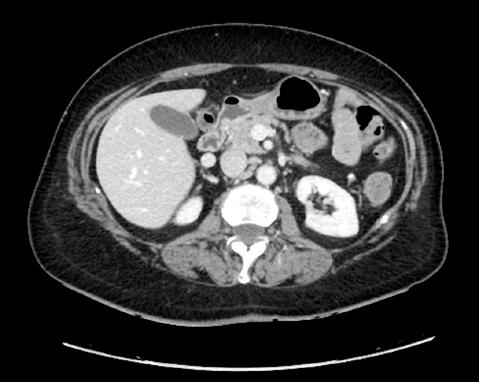

La stadiazione sistemica è stata effettuata mediante scintigrafia ossea e TC total body con mdc. La TC con mdc ha evidenziato la presenza di voluminosa eteroplasia mammaria di sinistra con aspetto multi nodulare plurifocale con estensione alla stazione linfonodale infraclaveare e ascellare di questo lato. Apparentemente conservato il piano di clivaggio rispetto alla parete toracica sottostante. Adenopatie interessanti le stazioni del mediastino superiore con diametro singolo sino a 4 cm ed estese bilateralmente lungo la linea mediana. Altre adenopatie in corrispondenza della stazione della carena tracheale e dell’ilo di sinistra. Alla cupola epatica destra evidente centimetrica nodulazione con enhancement marginale e verosimile componente necrotica centrale

sospetto per secondarismo. Centimetrica area di lisi verosimilmente secondaria del margine laterale sinistro al III medio dello sterno. Encefalo negativo. La scintigrafia ossea ha dimostrato un discreto iperaccumulo del tracciante osteotropo al margine sinistro del corpo sternale, dubbio per possibile infiltrazione di nota malattia.

Dopo 4 cicli di terapia, alla TC total body con mdc di ristadiazione di agosto 2023 si evidenziava remissione parziale della malattia in sede mammaria sinistra, linfonodale infraclaveare sinistra, ascellare e mediastinica e della metastasi epatica. Veniva però riscontrata la comparsa di lesioni cerebrali millimetriche e di linfonodi patologici in sede laterocervicale bilateralmente.

Alla RMN encefalo con mdc di approfondimento venivano evidenziate plurime lesioni ripetitive (almeno 10)

in sede sovratentoriale (diametro massimo 10x12 mm in sede temporale destra) circondate da alone di edema. Ulteriore lesione sospetta in sede sottotentoriale vermiana paramediana destra (2,5x2,5 mm circa) (figura 1a e 1b).

Alla TC total body con mdc di ristadiazione di febbraio 2024 (dopo 5 cicli di terapia con T-DXd) si è evidenziato un quadro di remissione completa in tutte le sedi di malattia interessate: encefalica, mammaria, epatica e linfonodale.

Figura 1a e 1b. Evoluzione della neoplasia mammaria primitiva dalla diagnosi in aprile 2023 alla risposta dopo 7 cicli di T-DXd in aprile 2024.

Figura 2a e 2b. Risposta intracranica completa dopo RT e T-DXd.